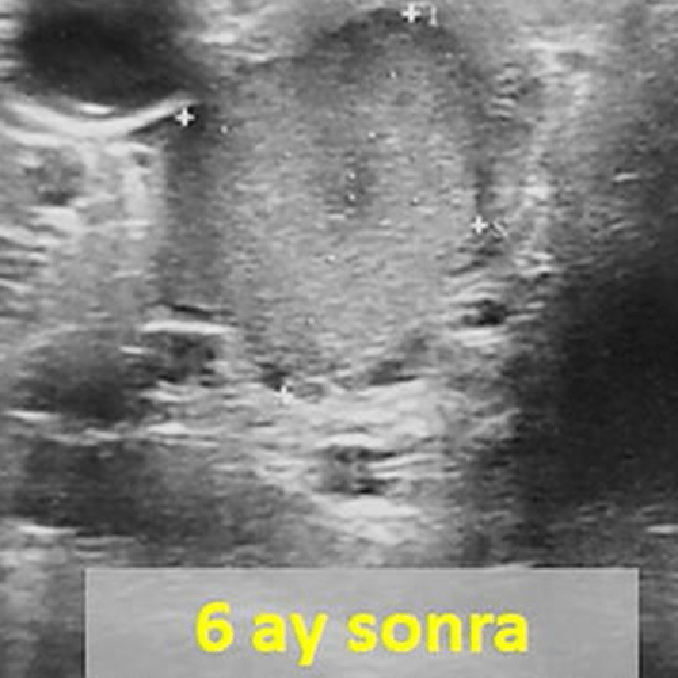

Sol tiroid lobunda 10 cm çaplı iyi huylu solid nodülü olan 31 yaşındaki erkek hastamıza embolizasyon tedavisi uygulandı. Altı ay sonra, nodülün hacmi %90 oranında azalmış ve boynun görünümü normale dönmüştür.